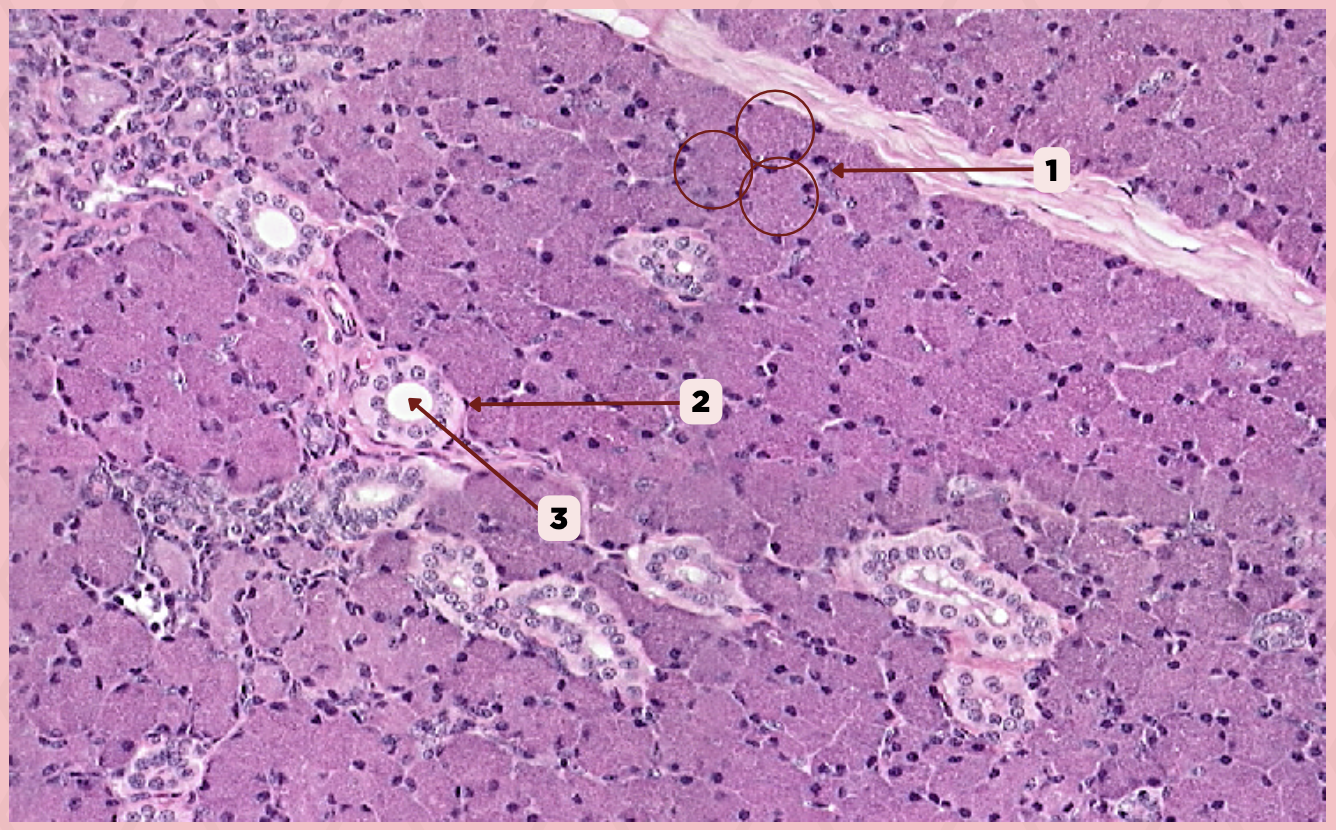

Parotid

Identify the specimen.

Secretory Acini

Identify the structure labeled as 1.

Myoepithelial Cell

Identify the structure labeled as 2.

Secretory Duct

Identify the structure labeled as 3.

Parotid

Identify the specimen.

Capsule

Identify the structure labeled as 1.

Lobule

Identify the structure labeled as 2.

Lobe

Identify the structure labeled as 3.

Connective Tissue

Identify the structure labeled as 4.

Parotid

Identify the specimen.

Adipocyte

Identify the structure labeled as 1.

Connective Tissue

Identify the structure labeled as 2.

Intercalated Duct

Identify the structure labeled as 3.

Striated Duct

Identify the structure labeled as 4.

Serous Gland

Identify the structure labeled as 5.